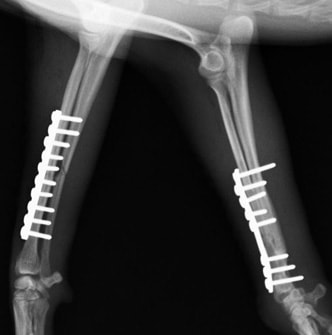

両前肢の骨折:橈骨尺骨骨折整復手術①

<右前肢>

来院時の右橈骨尺骨骨折のレントゲン写真

手術後のレントゲン写真

手術写真です。骨折端を露出させ、骨折端を合わせて、プレートとスクリューにて固定します。

<左前肢>

来院時の左橈骨尺骨骨折のレントゲン写真

両前肢の骨折:橈骨尺骨骨折整復手術②

手術前レントゲン写真①

手術後レントゲン写真①

手術前レントゲン写真②

手術後レントゲン写真②